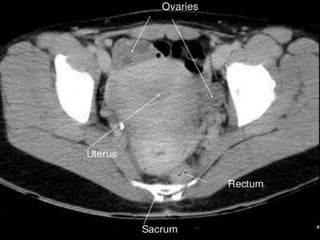

CT cross sectional anatomy.